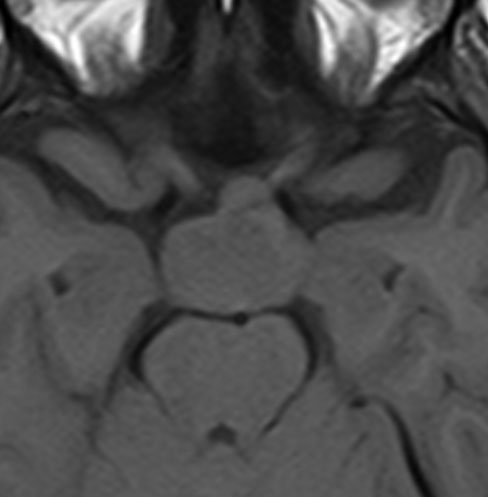

下垂体柄の周囲にのう胞性腫瘍があります。T1強調画像では等信号,T2強調画像ではまだらな信号になっています。23年という長い経過から液状内容物が固形化したものと推定されます。T2で低信号となる部分があるのですが,黄色肉芽腫とは異なる像です。

下垂体柄は長く伸びています。のう胞による長期の圧迫のため斜台上部がerosionになって凹んでいます。トルコ鞍内の中間葉の位置に典型的な小さなラトケのう胞(黄色矢印)がみられますが,これは長年変化していませんでした。